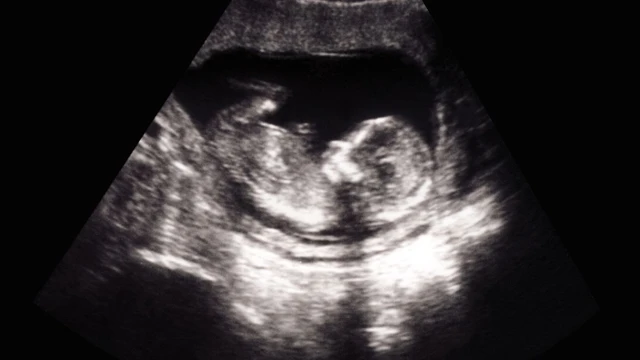

Việc ghi nhớ các mốc siêu âm quan trọng giúp mẹ bầu kiểm soát tốt sự phát triển của thai nhi qua từng giai đoạn, giúp bác sĩ phát hiện sớm bất thường và chuẩn bị tốt cho quá trình sinh nở. Bài viết dưới đây sẽ giúp mẹ bầu hiểu rõ từng mốc cần thiết và không bỏ lỡ bất kỳ thời điểm quan trọng nào.